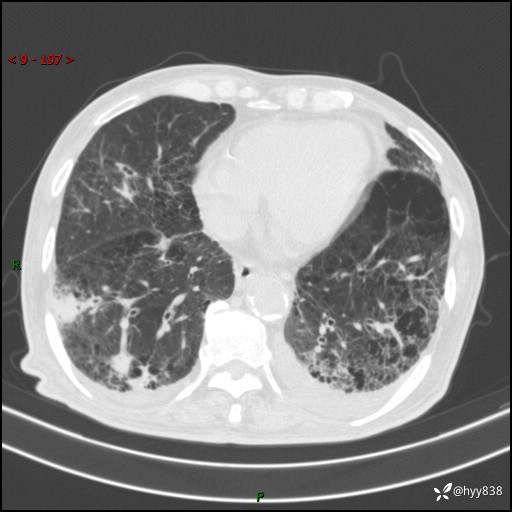

老年男性,间断咳嗽咳痰20余年,加重伴发热1天。呼吸科疑难病例讨论---结果公布

主诉:间断咳嗽咳痰20余年,加重伴发热1天

简要病史:家属代诉患者于20余年前无明显诱因出现咳嗽咳痰,痰为白色泡沫状,未行特殊治疗,不伴胸痛、胸闷、气喘、咳血等不适,1天前上午患者无明显出现发热,查体温39℃,伴咳嗽,咳痰无力,自行予以物理降温对症治疗,今晨2点左右再次出现发热,体温达40℃,自行服用复方氨酚烷胺对症治疗,凌晨3点左右复测体温38.2℃,现患者为求进一步诊治于今日就诊于我院门诊,行胸部CT提示双肺感染,遂以“肺部感染”收入我科。 患者本次起病来精神、食欲、睡眠欠佳,体力下降,体重无明显变化。

辅助检查:CT

讨论:病变性质?

胸部CT平扫